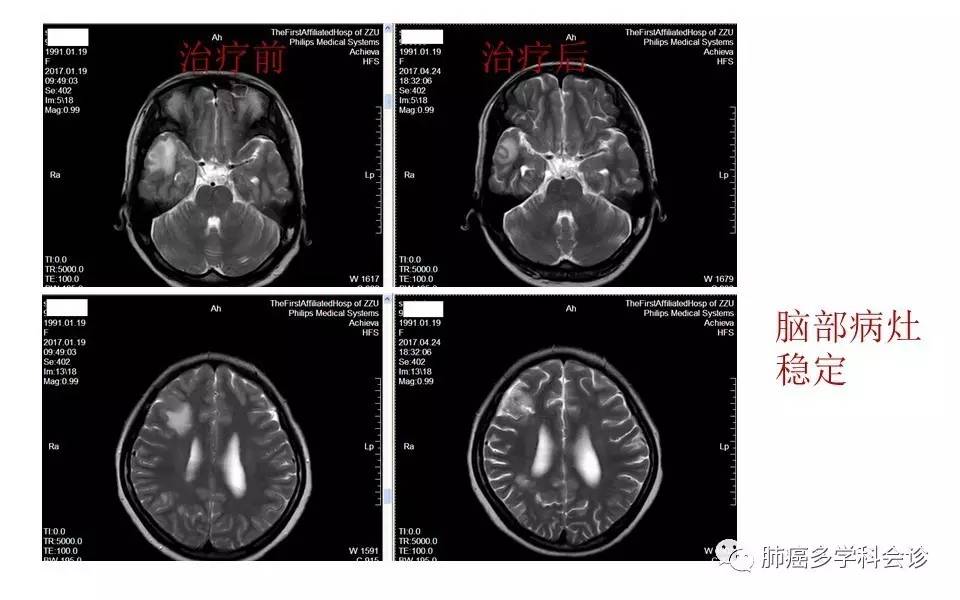

绝处逢生:NGS助力肺癌精准医疗--记1位ROS-1阳性者